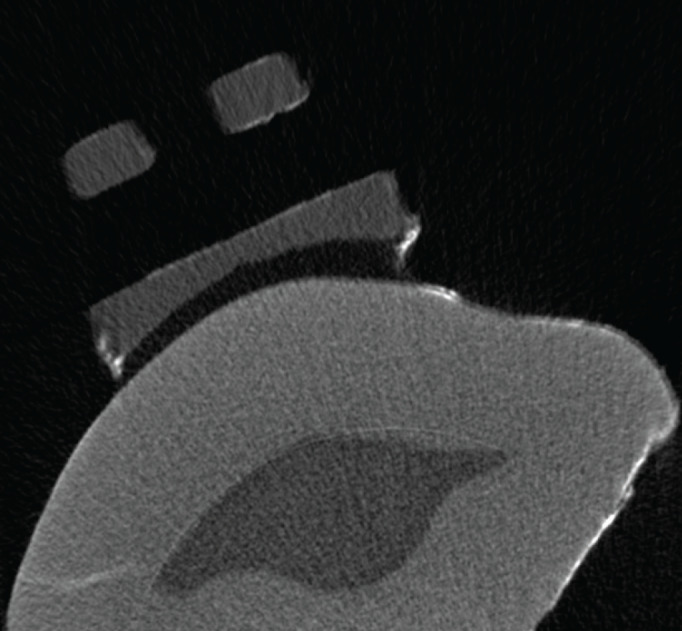

Methods: Forty extracted human maxillary premolar teeth were randomly divided into five groups. According to the groups, adhesive coated and conventional bracket systems were bonded to the tooth surfaces with the specified adhesive agents. To simulate a six-month oral environment, all teeth were subjected to a thermal cycle procedure. Micro-computed tomography (micro-CT) was used to view and measure the microleakage. Kruskal-Wallis test was used to compare the parameters and Mann-Whitney U test was used for the determination of the group that caused the difference. For intragroup comparisons Wilcoxon signed-rank test was used.

Results: Microleakage volume (mm3) and microleakage percentage (%) measured in Blugloo™ group was found significantly lower (p<0.05) then other groups. There was no significant difference in microleakage volume (mm3) and percentage (%) in comparison of gingival and occlusal regions (p>0.05).

Conclusion: Adhesive precoated flash-free brackets were not shown a significant difference compared to their conventional equivalent for microleakage volume. The brackets bonded with Blugloo™ adhesive were showed significant less microleakage than the other groups.